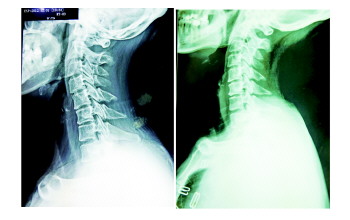

| 颈椎治疗前 颈椎治疗后 |